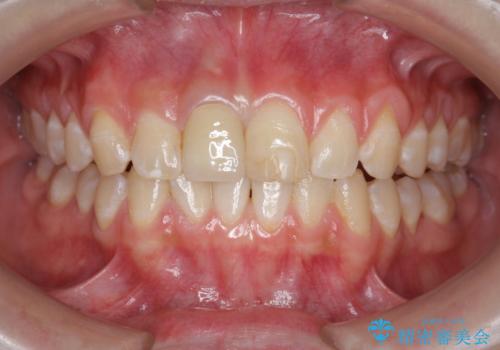

前歯をきれいにしたい ジルコニアクラウンによる審美治療

- 前歯の見た目の改善を求めて来院されました。

ジルコニアクラウンによる審美性の改善を計画します。

失活歯のため捻転を改善し、根管治療は特に希望されなかったのでそのままとしました。

- 11万円(仮歯・ジルコニアクラウン)費用は治療当時の料金となります

今回失活歯であったため捻転を取り反対側の前歯に揃えて補綴を行うことができました。